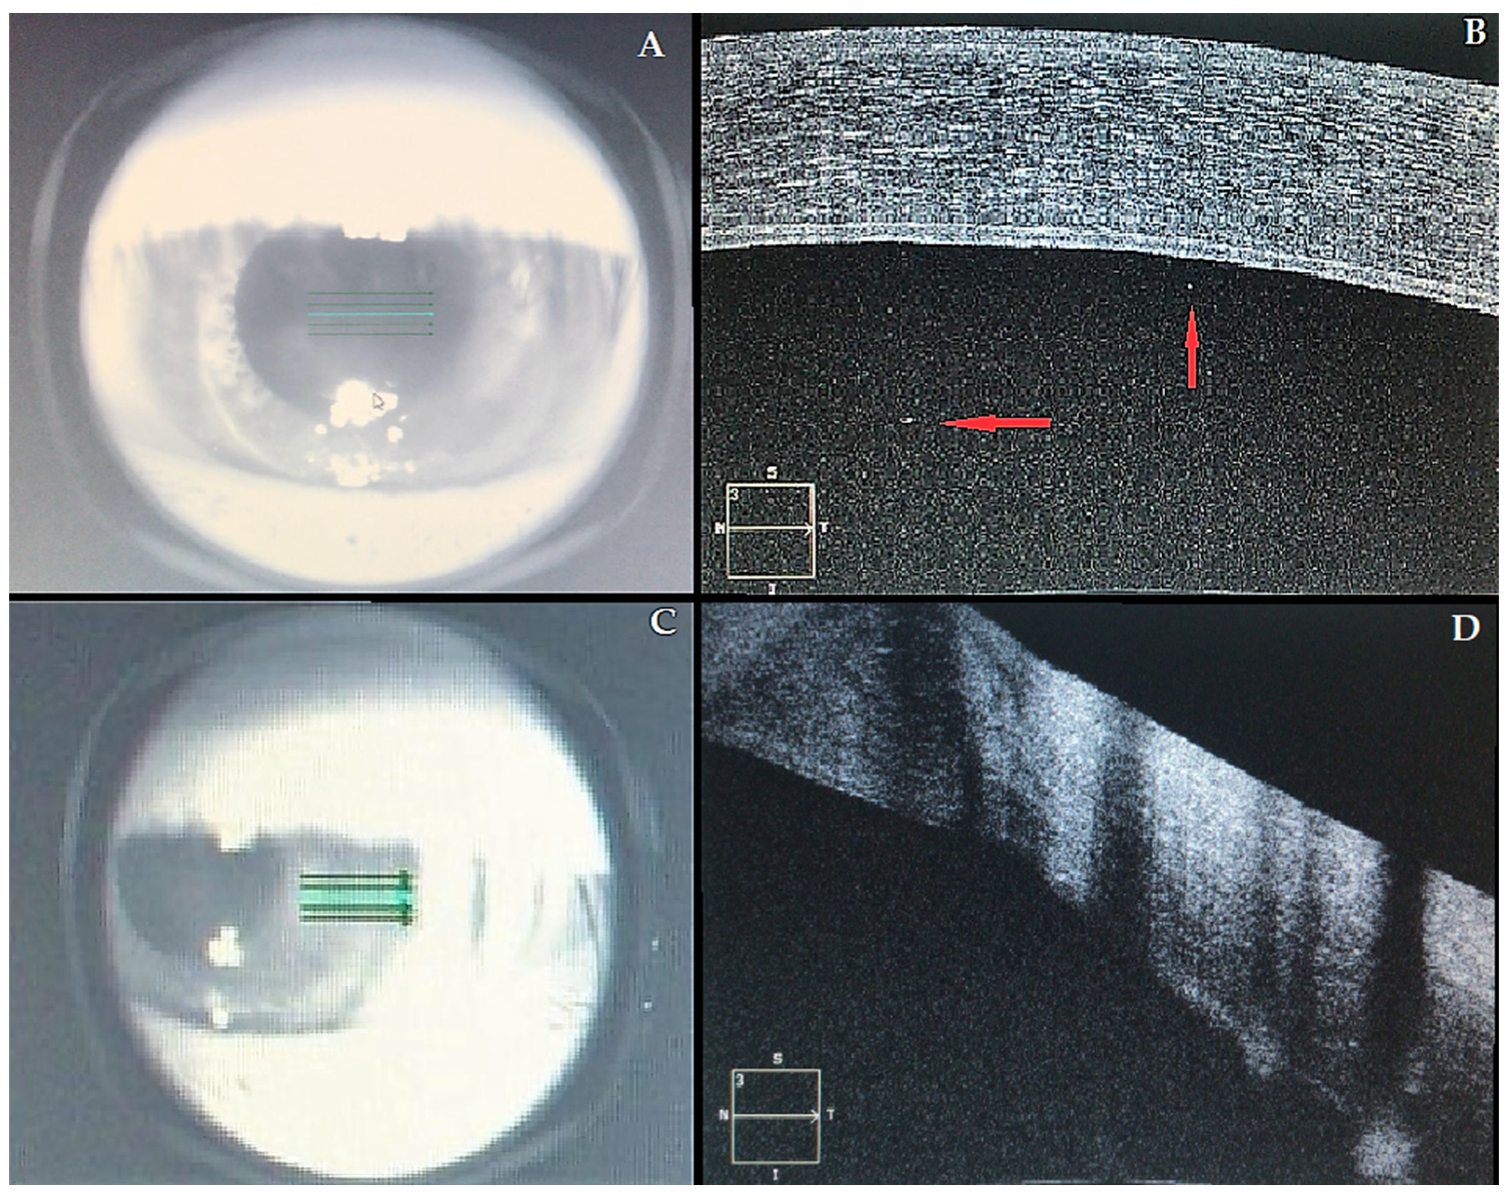

At presentation, her left best-corrected visual acuity (BCVA) was counting fingers, compared to 20/30 recorded six months before. Intraocular pressure was 12 mm Hg. Slit-lamp biomicroscopy revealed ciliary injection, diffuse corneal edema within the graft, keratic precipitates, Descemet folds, and anterior chamber (AC) cells were noted, indicating corneal graft rejection. The right eye was unremarkable. Fundus examination was normal in both eyes. Anterior segment OCT confirmed a series of morphological changes (corneal thickening, subepithelial bullae, internal cornea folds, hyper-reflective points in AC, irregularities of the endothelium). Central corneal thickness (CCT) was 692 μm, compared to 560 μm of a previous visit (Figure 1). An AC aqueous sample was examined by polymerase chain reaction (PCR), and it was negative for cytomegalovirus, herpes simplex virus, and varicella-zoster virus. The complete blood count was normal. However, a severe vitamin D deficiency (circulating 25-hydroxyvitamin D [25(OH)D] concentration of 9 ng/mL) was detected. (Table 2).

Figure 1. Acute corneal graft. (AC) Infrared images of the left eye; (BD) correspondent OCT images. Central cornea (A,B): in Figure 1B, it is possible to observe a marked corneal edema and a series of morphological changes (see text). Red arrows indicate a number of inflammatory floaters in the anterior chambre. Transition area (C,D) between the recipient’s cornea (normal thickness) and the graft (thickened by edema).